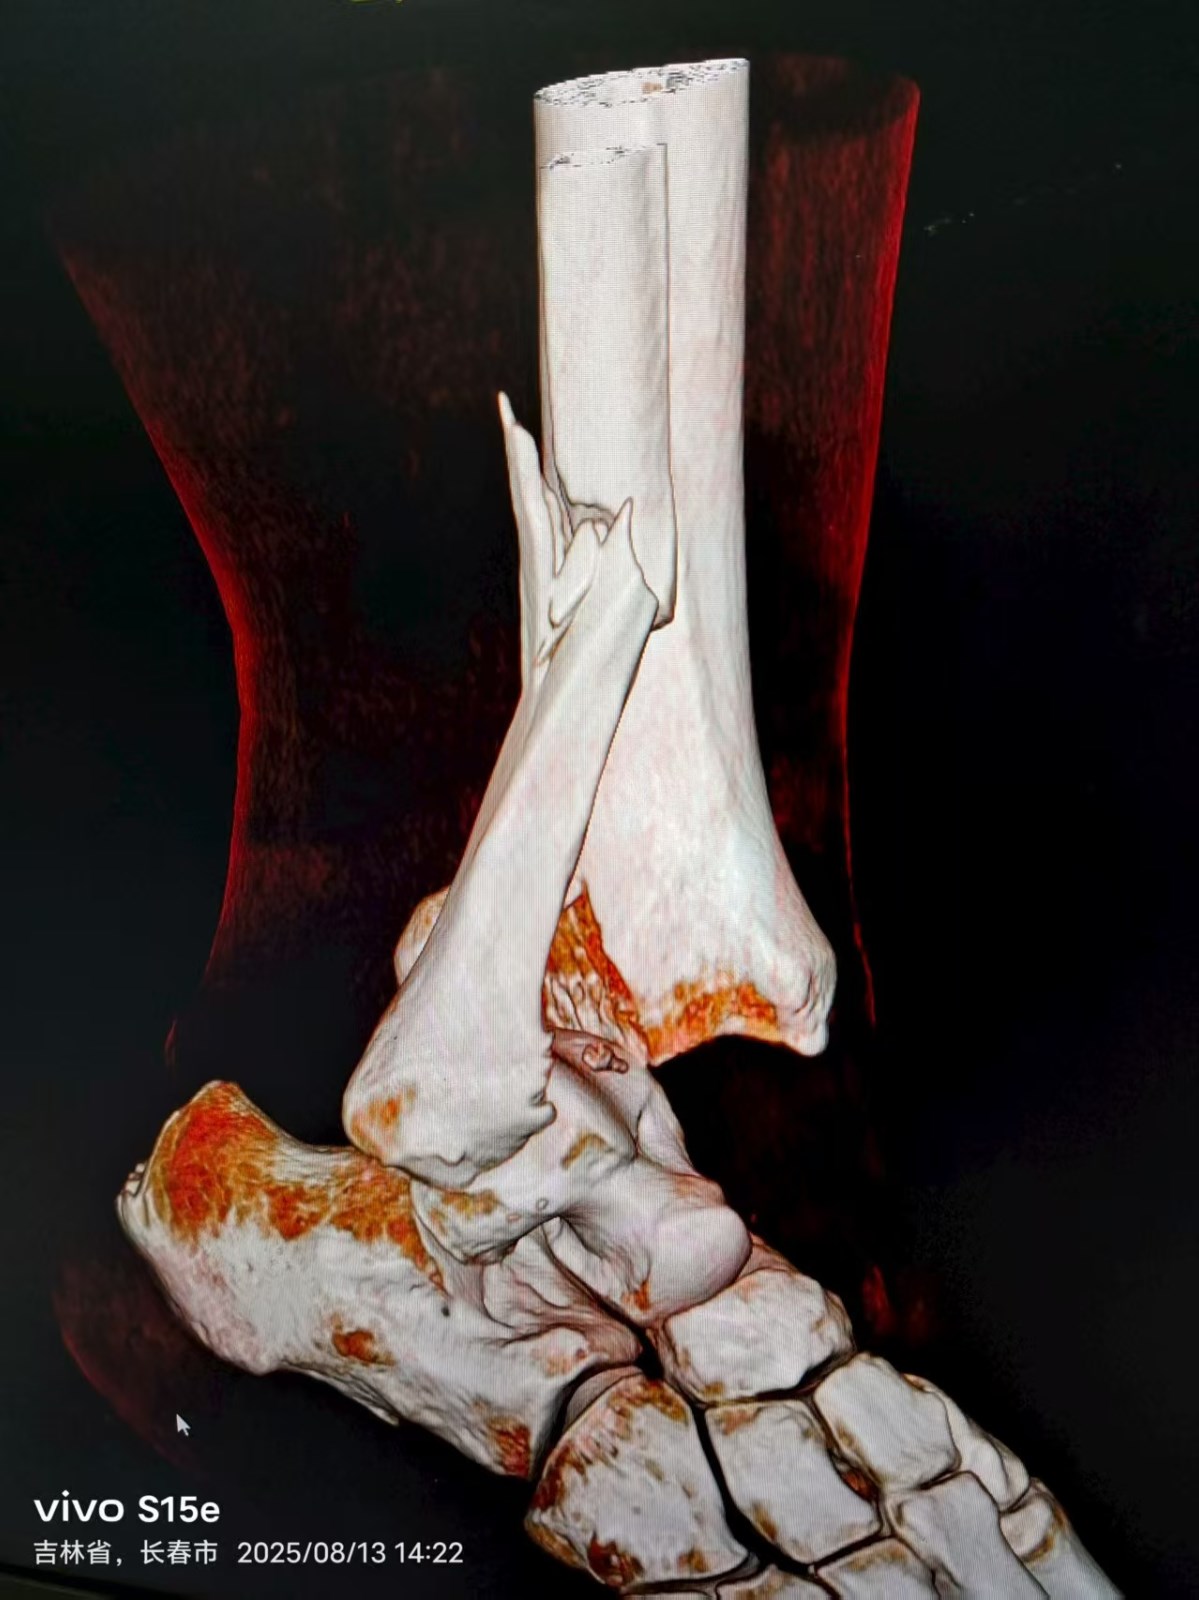

患者王某,骑电动车在上班途中,被迎面急驰而来的快递员电动车撞倒,导致右踝关节受伤,被我院120急救车接到医院,经摄片检查,确诊患者右踝关节骨折伴脱位,需要住院手术治疗。

8月14日上午,董庆武主任带领骨科团队,在全麻麻醉下,为患者行右外踝切开复位锁定钛板螺钉内固定,后踝切开复位拉力螺钉内固定,术中,专家团队凭借精湛医术和丰富经验,精准地对骨折部位进行复位和固定,术后摄片效果满意。